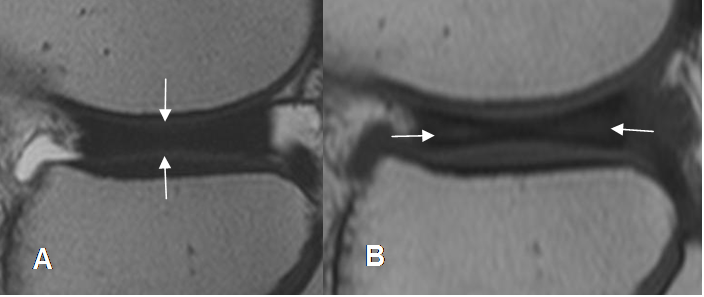

Se diagnostica si en la RM, se aprecia la porción media del menisco en 3 o mas cortes sagitales contiguos, de 5 mm de espesor, entre el cuerno anterior y posterior. (47). (Fig 190).

Fig 190. Menisco discoide.

A: RM sagital en T2. Prominencia en la parte media del menisco, por configuración discoide.

B: RM sagital en T2. Menisco discoide, con cambios degenerativos en ambos cuernos.